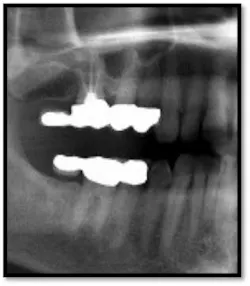

Ill-fitting posterior crowns are a plaque and food trap which are contributing factors in posterior inflammation and pocketing

UR/LR Pre TxThe tissues around the posterior crowns are almost bluish in color(above left)UL/LL Pre Tx:

TX FM Perioscopy with local anesthetic FM LANAP Surgical Procedure •bone sounding was performed on all teeth included in this procedure •occlusal adjustment performed resulting in reduction in centric prematurities •Orthodontic referral for anterior spacing •3 month periodontal maintenance14 months post TreatmentPocket reductions of up to 4mm